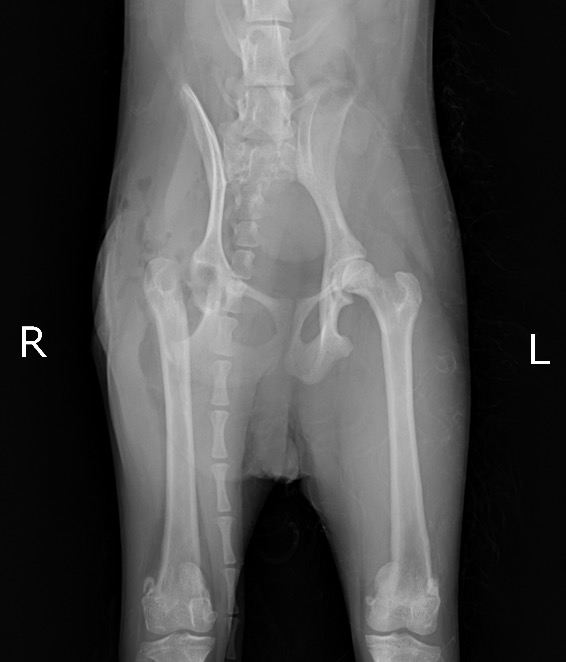

X線検査において、右大腿骨頭部のの剥離骨折が認められ(赤矢印)、背景にレッグカルベペルテス病(LCPD、無菌性虚血性大腿骨頭壊死症)(以下LCPD)の存在が疑われました。

また、右側の大腿部の筋萎縮が顕著に認められました(青線)。

これは廃用性萎縮といい、しばらくの間、股関節の痛みから右後ろ足をかばって生活していたためと考えられます。

術前X線 右大腿骨頭部の骨折(赤矢印)/ 大腿部の筋萎縮(青線)